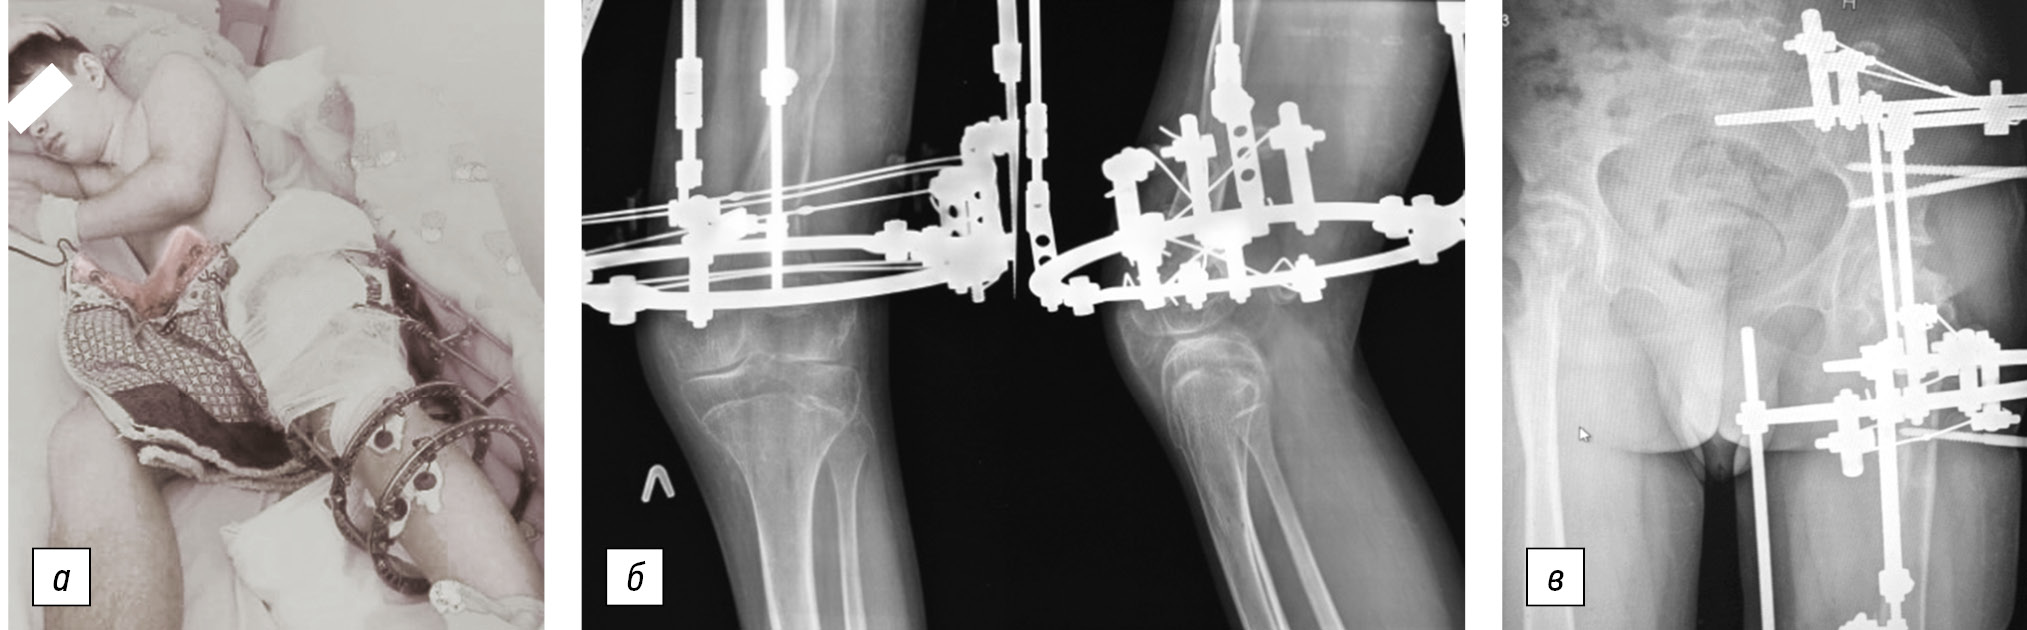

In this situation, lameness, leg size discrepancy, axial deformity, pelvic torsion during walking, and limited left knee joint extension became an indication for staged surgical treatment. The hip joints retained full extension with free flexion of up to 90°, abduction possibility of 25°–30°, and total rotation on each side of 15°–20° before the last surgical correction of the left femur in its distal part. The support ability of the left knee joint was reduced due to the rigid restriction of the extension within 15°, flexion of 30°, and an external rotational positioning of the left lower limb. A corrective detorsion-varus extensor osteotomy with fixation using the Ilizarov apparatus was performed in February 2021 to restore the left lower limb length and eliminate the left femur deformity in its lower third. Additionally, the hip joint was fixed with an apparatus to maintain stability and ensure unloading of the left hip joint at the time of distraction and for 4 weeks after its completion (Fig. 4). The load on the operated lower limb was permitted the next day postoperatively. The total left femur elongation was 4 cm along with deformity correction.

Fig. 4. Photograph of the patient (a) and left knee (b) and hip (c) joint radiograph at the stage of left femur lengthening